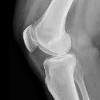

Рентген суставов. Метод лучевой диагностики, позволяющий выявлять патологические изменения в костных структурах и окружающих околосуставных тканях, а также отслеживать динамику изменений рентгенологических симптомов при различных заболеваниях. Рентгенологические признаки, указывающие на повреждение сустава, могут включать сужение или расширение суставного пространства, утолщение и затвердение мягких тканей, кальцификации, кистозное просветление костной ткани, эрозию суставных поверхностей, остеофитов, нарушение нормальных пространственных отношений между суставами. голова и полость ; Контрастная артрография, пневмоартрография, а также компьютерная и магнитно-резонансная томография суставов используются при диагностике ревматических заболеваний и травм наряду со стандартной рентгенографией суставов.

Основой рентгенографии суставов является способность тканей различной плотности поглощать различные количества рентгеновских лучей, плотная кость поглощает большое количество радиации, мягкие ткани - небольшое количество. Используя специальное устройство, рентгенолог направляет рентгеновский луч на сустав. Лучи проходят через ткань и образуют изображение на пленке за суставом. Костные структуры сустава имеют почти белый вид, мягкие ткани имеют различные оттенки темно-серого.

Совместная рентгенография в Москве широко используется в травматологии, ортопедии и ревматологии. Если указано, он используется в челюстно-лицевой хирургии, онкологии и в других областях медицины. Рентген суставов позволяет диагностировать переломы, переломы, вывихи, подвывихи, артрозы, артриты, врожденные аномалии развития, нарушения обмена веществ, доброкачественные и злокачественные примитивные опухоли и метастатические поражения суставных концов костей при различных онкологических заболеваниях. При введении атмосферных или контрастных агентов рентгенография суставов может использоваться для выявления патологии хрящей и мягких тканей (связок, менисков, суставных мешков).

Используя это исследование, можно определить количество, положение, степень и направление движения костных отломков при внутрисуставных и периартикулярных переломах, выявить нарушения конгруэнтности конечностей суставов при вывихах и подвывихах. Рентгенография суставов полезна для локального или диффузного уменьшения или увеличения плотности костей (остеопороз и остеосклероз), наличия внутрисуставной жидкости при гемартрозе и синовите, сужения суставного пространства при артрозе, расширения суставного пространства при разрыве связки.

Рентген суставов позволяет обнаруживать деформации суставов концов кости в результате остеоартрита, артрита или неправильно связанного перелома, а также выявлять краевые новообразования костей и очаги кальцификации в мягких тканях сустава (связка, капсула сустава, синовиальная оболочка, кожа, мышцы и ). жировая ткань). Кроме того, при исследовании рентгеновских лучей вы можете увидеть опухоли, расположенные в костях (если смотреть детально, вы можете оценить размер, контуры, структуру) и окружающие мягкие ткани (для точной оценки требуются дополнительные исследования - КТ или МРТ).